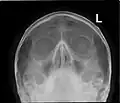

CT scans, radiographs (X-rays) and other illustrations

Paranasal sinuses radiograph (occipitofrontal) -